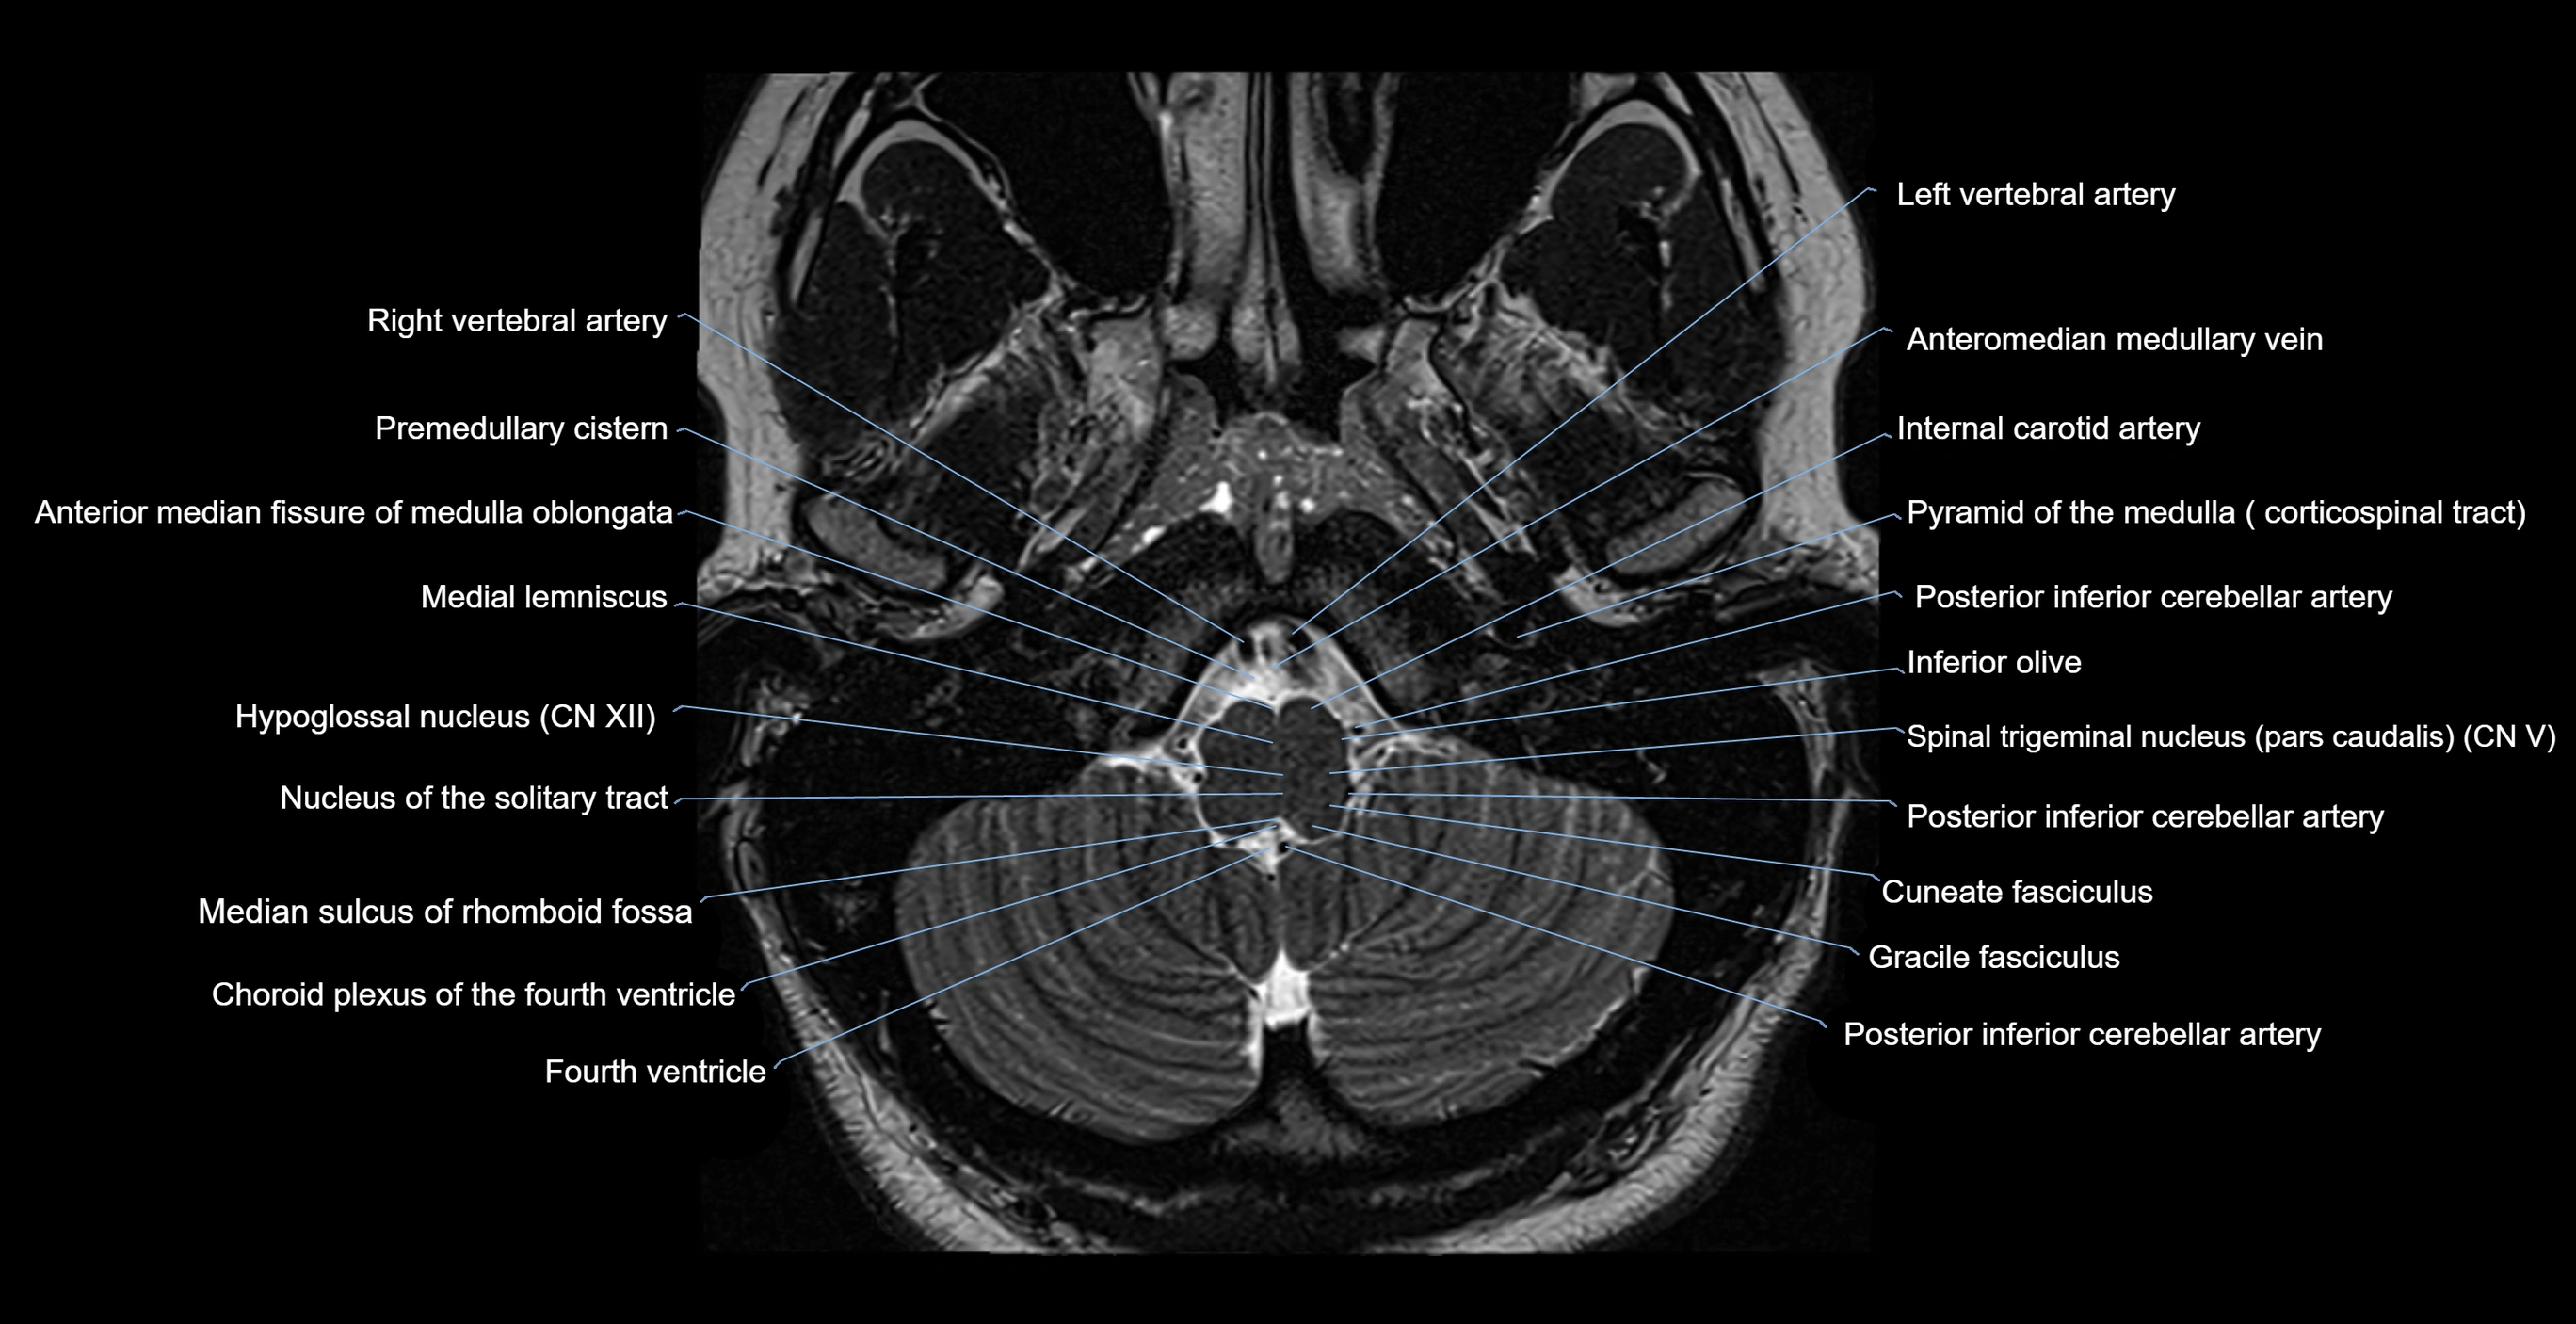

MRI images